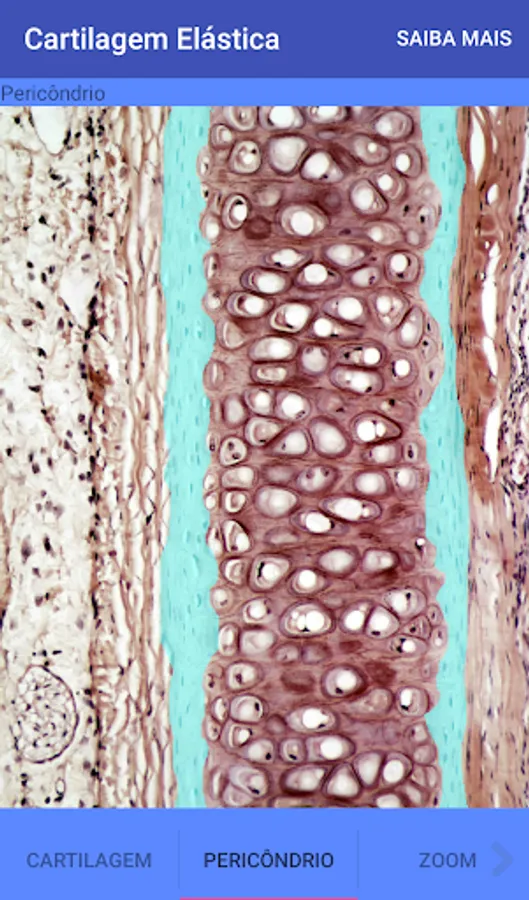

Elastic Cartilage